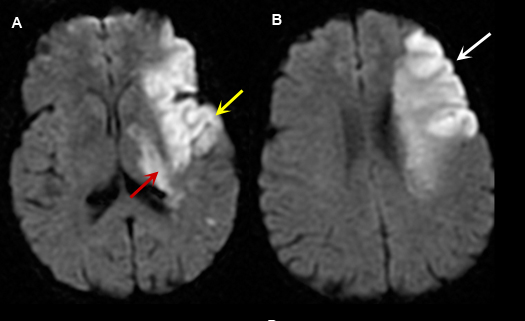

Figure 4: MR Images (DWI)

|

Left Middle Cerebral Artery Territory Acute Stroke

Case 4:

Imaging findings: Figure 4

- A and B: Diffusion weighted images shows areas of acute infarction as bright signal due to intracellular cytotoxic edema, restricting movement of water molecule in and out of the cell.

- In figure A, left temporal lobe acute infarction (yellow arrow) and left lateral basal ganglia-thalamic regions (red arrow) are noted.

- Left frontal lobe infarct (arrow) is shown in Fig. B.

|